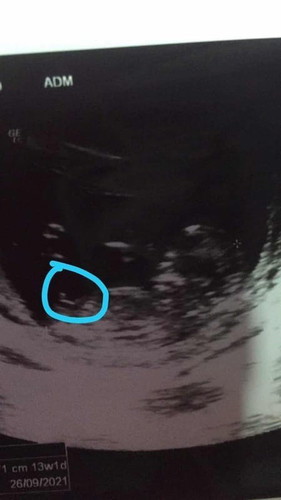

เมื่อวานไปหาหมอ เรา13วีค. ซาวด์เห็นจู๋เลยตกใจทำไมเห็นเพศเร็วจัง. แต่ตอนท้องแรกรู้ตอน5เดือนค่ะ. เลยสงสัยว่าชายชัวไหมค่ะแบบนี้ มีบ้านไหนเห็นเร็วมั้งค่ะ

ชายน่าจะดูง่ายกว่าญ เเต่ก็ไม่เเน่ค่ะเเม่รอลุ้นอีกครั้ง